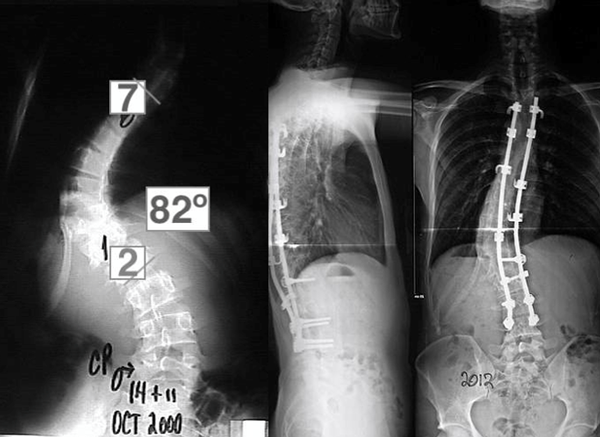

La malformación de Chiari tipo I permaneció sin cambios, pero se observó una progresión de la curva escoliótica a 350°. A la edad de 12 años y 3 meses, el paciente fue intervenido quirúrgicamente de la malformación de Chiari tipo I.

Se realizó un abordaje con craniectomía suboccipital asociada a resección del arco posterior en C1. Dos años más tarde, se constató que dicha escoliosis había progresado a 82° (Figura 3) y se decidió hacer la fusión espinal posterior instrumentada de T4-L4 con corrección de la curva a 390°.

Figura 3. Espinograma, frente. Progresión curva de Cobb y su corrección mediante instrumentación toraco-lumbar.